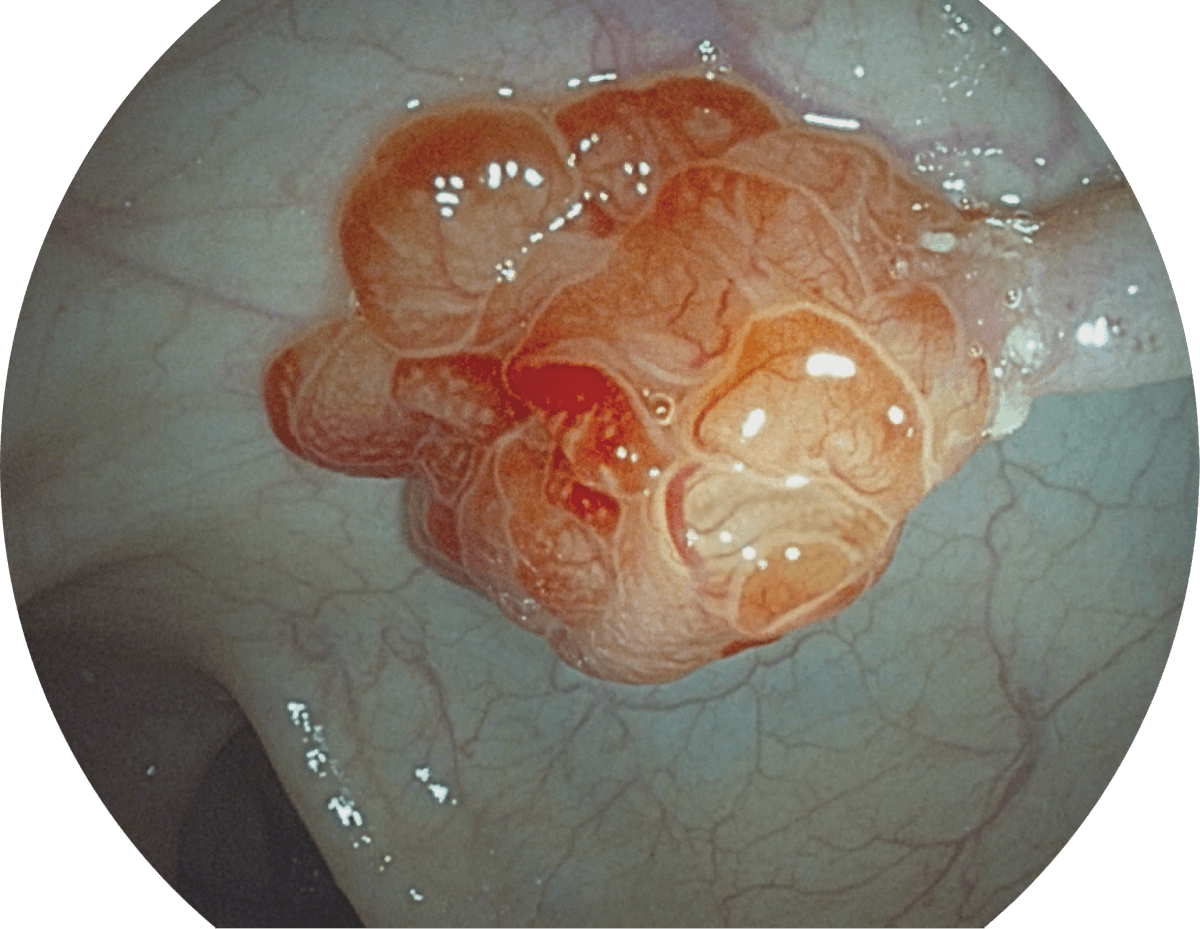

具有聚谱成像技术(SFI)及光电复合染色成像技术(VIST),可完美呈现粘膜细节及病变特征。

(Spectral Focused lmaging, SFI)

SFI